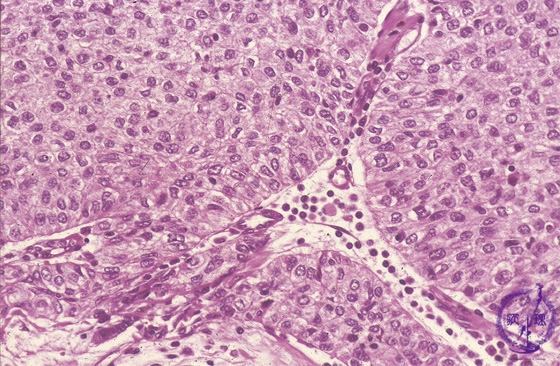

Microscopic view (high power view): Type B3 thymoma (epithelial thymoma) (WHO classification). Large, polygonal epithelial tumor cells grow in sheets without infiltrating lymphocytes. The perivascular spaces (★) seen centrally surrounding small capillaries (arrow) are a finding specific to thymoma.